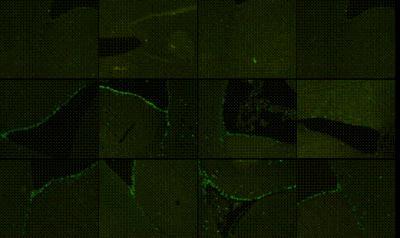

EGb761 improved the proliferation of neural stem cells in the subependymal zone of vascular dementia rats (immunofluorescence staining). The presence of green particles in the nucleus was the marker of BrdU-positive cells. BrdU: 5-Bromo-2-deoxyuridine.

(Photo Credit: Neural Regeneration Research)